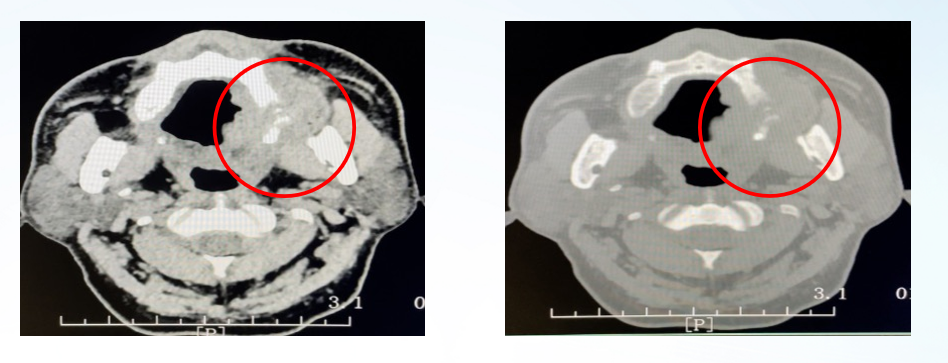

疾病进展:2020年10月,患者自觉左上颚肿块,口腔CT提示:左上颚软组织肿块(38mm),邻近左上颌骨骨质破坏伴软组织肿块,考虑转移瘤(MT)。

图18、左上颚肿块(2020-10-22)

图19、口腔增强CT(2020-10-22)

口腔活检病理:左上颚软组织肿块穿刺活检术,恶性肿瘤,结合病史,考虑结肠癌转移。